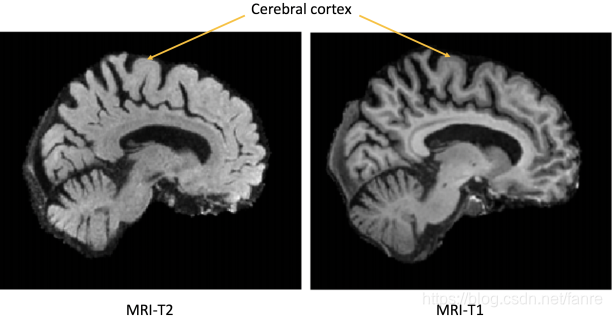

不同的成像技术对体内组织有不同的反馈,所以才需要多模配准,来提供更多的信息。像MRI-T1可以区分脑部健康的组织,MRI-T2更容易反馈出一些高亮的异常结构,例如肿瘤。

图1.1 MRI-T1和MRI-T2同一个病人的脑部扫描。不同的组织对比,MRI-T1要比MRI-T2更好,最明显的是大脑皮层的轮廓。